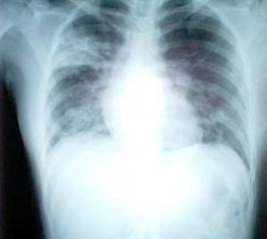

SARS患者患病八天的胸透照片